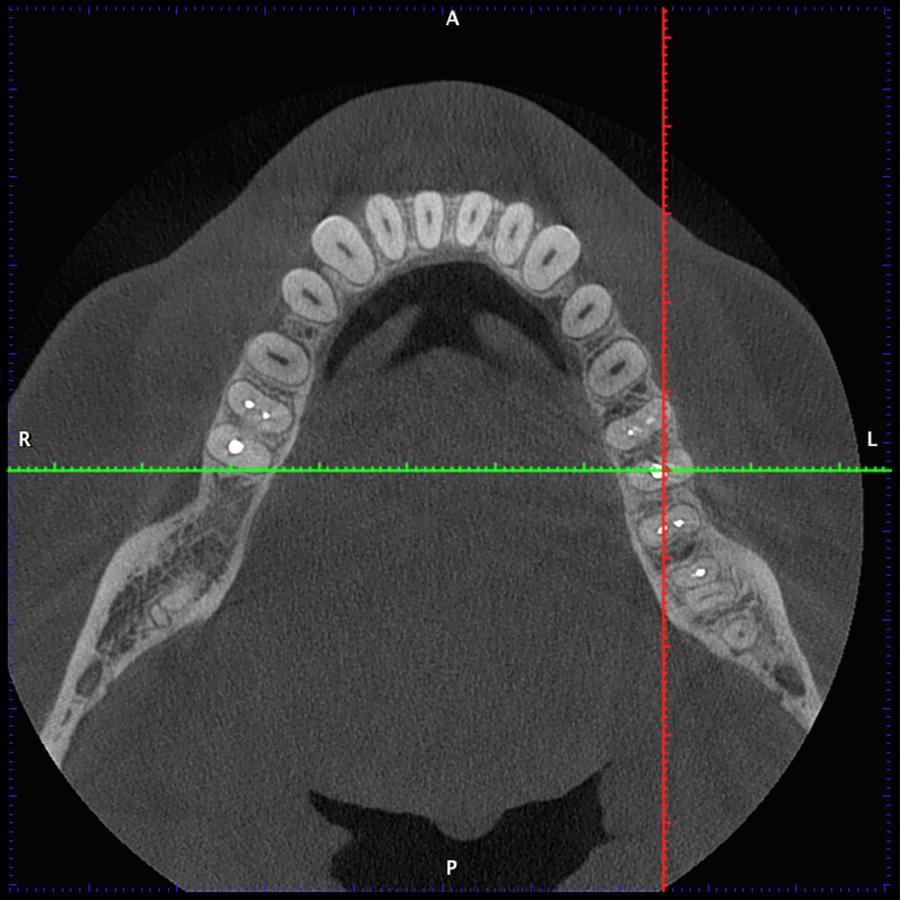

Комп'ютерна томографія

Щелепно-лицева діагностика

Мережа діагностичних центрів "МАЙРЕЙ ЛАБ" забезпечує точну та надійну діагностику

щелепно-лицевої ділянки з мінімальним ризиком для пацієнтів.

Ми використовуємо найсучасніше обладнання відомого виробника PLANMECA, що дозволяє отримувати високоякісні зображення за короткий час. Крім того, ми маємо власний сервер, на якому створюємо окрему скриньку для кожного лікаря, що забезпечує максимальну зручність та ефективність роботи.

3D цефалометричний аналіз є сучасною технологією, яка дозволяє отримувати точніші,

комплексніші та надійніші дані про зубну та скелетну структуру. Ця технологія може стати

великим кроком в перед для ортодонтів, які хочуть забезпечити найкраще можливе лікування

своїх пацієнтів.

Основні переваги 3D цефалометричного аналізу:

Точність: 3D цефалометричний аналіз забезпечує точніше визначення розмірів та відстаней між

зубами та кістковими структурами.

Комплексність: ця технологія дозволяє отримувати детальні дані про різні структури, такі як

кістка та м'язи, що дозволяє ортодонтам докладніше досліджувати деякі патології та планувати

лікування.

Надійність: 3D цефалометричний аналіз дозволяє отримувати надійніші результати, оскільки

виключає можливість помилок, пов'язаних зі спотворенням або перекриттям зображень.